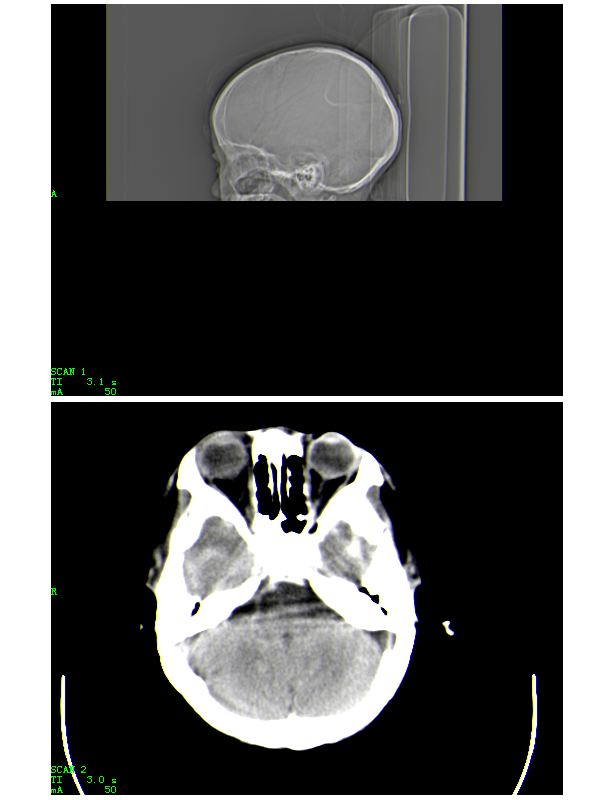

男,13岁,头部外伤后头痛、呕吐三小时就诊,查体,见小孩精神状态尚可,面部,嘴唇青紫明显,后作心脏彩超证实为“发四”,有复查片,大家先看看首诊片,考虑什么

患者,男,15岁。发现心脏杂音12年。因心慌气短、胸闷等症状加重而就诊。急诊实验室检查:红细胞平均体积0.95,红细胞压积0.820,红细胞容积分布宽度0.166,红细胞数8.55x10^12/l,血红蛋白(hb)267g/l。就诊前及就诊期间无外伤史,未服用或注射高密度元素制剂,未行影像造影检查和增强检查。急诊ct平扫示:颅内血管系统边缘清楚,但其内密度明显均匀增高(ct值约73hu),高于脑实质密度,所见颅内脑沟显示边界清楚,脑脊液及脑实质密度属正常平扫密度范围(图1-4)。影像诊断:高血红蛋白脑血管致密改变。

说明:ct值的测定以纯水为0hu,随着水中成分的增加,液体对x线的吸收增加,进而ct值增高。人体血液中影响ct值的主要成分是有形成分红细胞和血浆中的蛋白质,尤其室含铁的hb,其占血液中蛋白质总量的大部分,亦是引起血液ct密度变化的主要因素。hb含量与ct值间具有相关性,noman等的研究表明hb含量每改变10g/l,相应ct值变化为1.86hu。而本例患者的hb高达267g/l,可以解释颅内血管ct值明显升高的原因。本病主要应与蛛网膜下腔出血相鉴别,鉴别要点:(1)本病的高密度血管网络旁仍见清晰、正常低密度脑脊液影;(2)临床没有急性颅内出血的症状何体征。

感谢大家的关注,本例我们最后诊断为高血红蛋白症所致的脑血管改变,患者血红蛋白258g/l

人体血液中影响ct值的主要成分是有形成分红细胞和血浆中的蛋白质,尤其室含铁的hb,其占血液中蛋白质总量的大部分,亦是引起血液ct密度变化的主要因素。hb含量与ct值间具有相关性,noman等的研究表明hb含量每改变10g/l,相应ct值变化为1.86hu。

本病主要应与蛛网膜下腔出血相鉴别,鉴别要点:

(1)高密度血管网络旁仍见清晰、正常低密度脑脊液影;

(2)临床没有急性颅内出血的症状何体征。